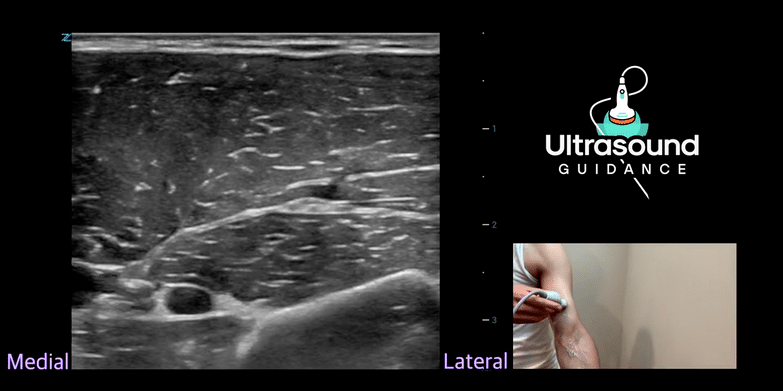

| Infraclavicular Brachial Plexus Injection | Radial Nerve | |

| Supraclavicular Brachial Plexus Injection | ||